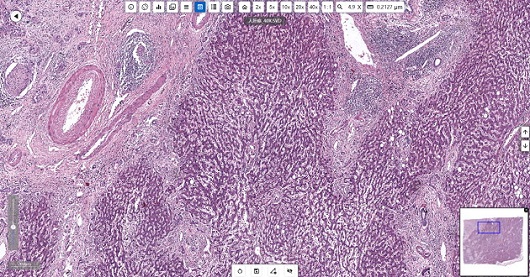

明美切片掃描儀MDS4掃描的人肝癌切片

在應對新發傳染病、慢性病及全球公共衛生挑戰中,疾控中心的病理學實驗室承擔著疾病診斷、病原體鑒定及公共衛生事件溯源等關鍵任務。光學顯微鏡作為實驗室的基礎設備,在組織病理學分析、病原體檢測及機制研究中發揮著不可替代的作用。

光學顯微鏡在疾控中心病理學實驗室中貫穿疾病診斷、機制研究及公共衛生決策的全流程。它是疾病診斷的“眼睛”、科學研究的“探針”、防控決策的“基石”。